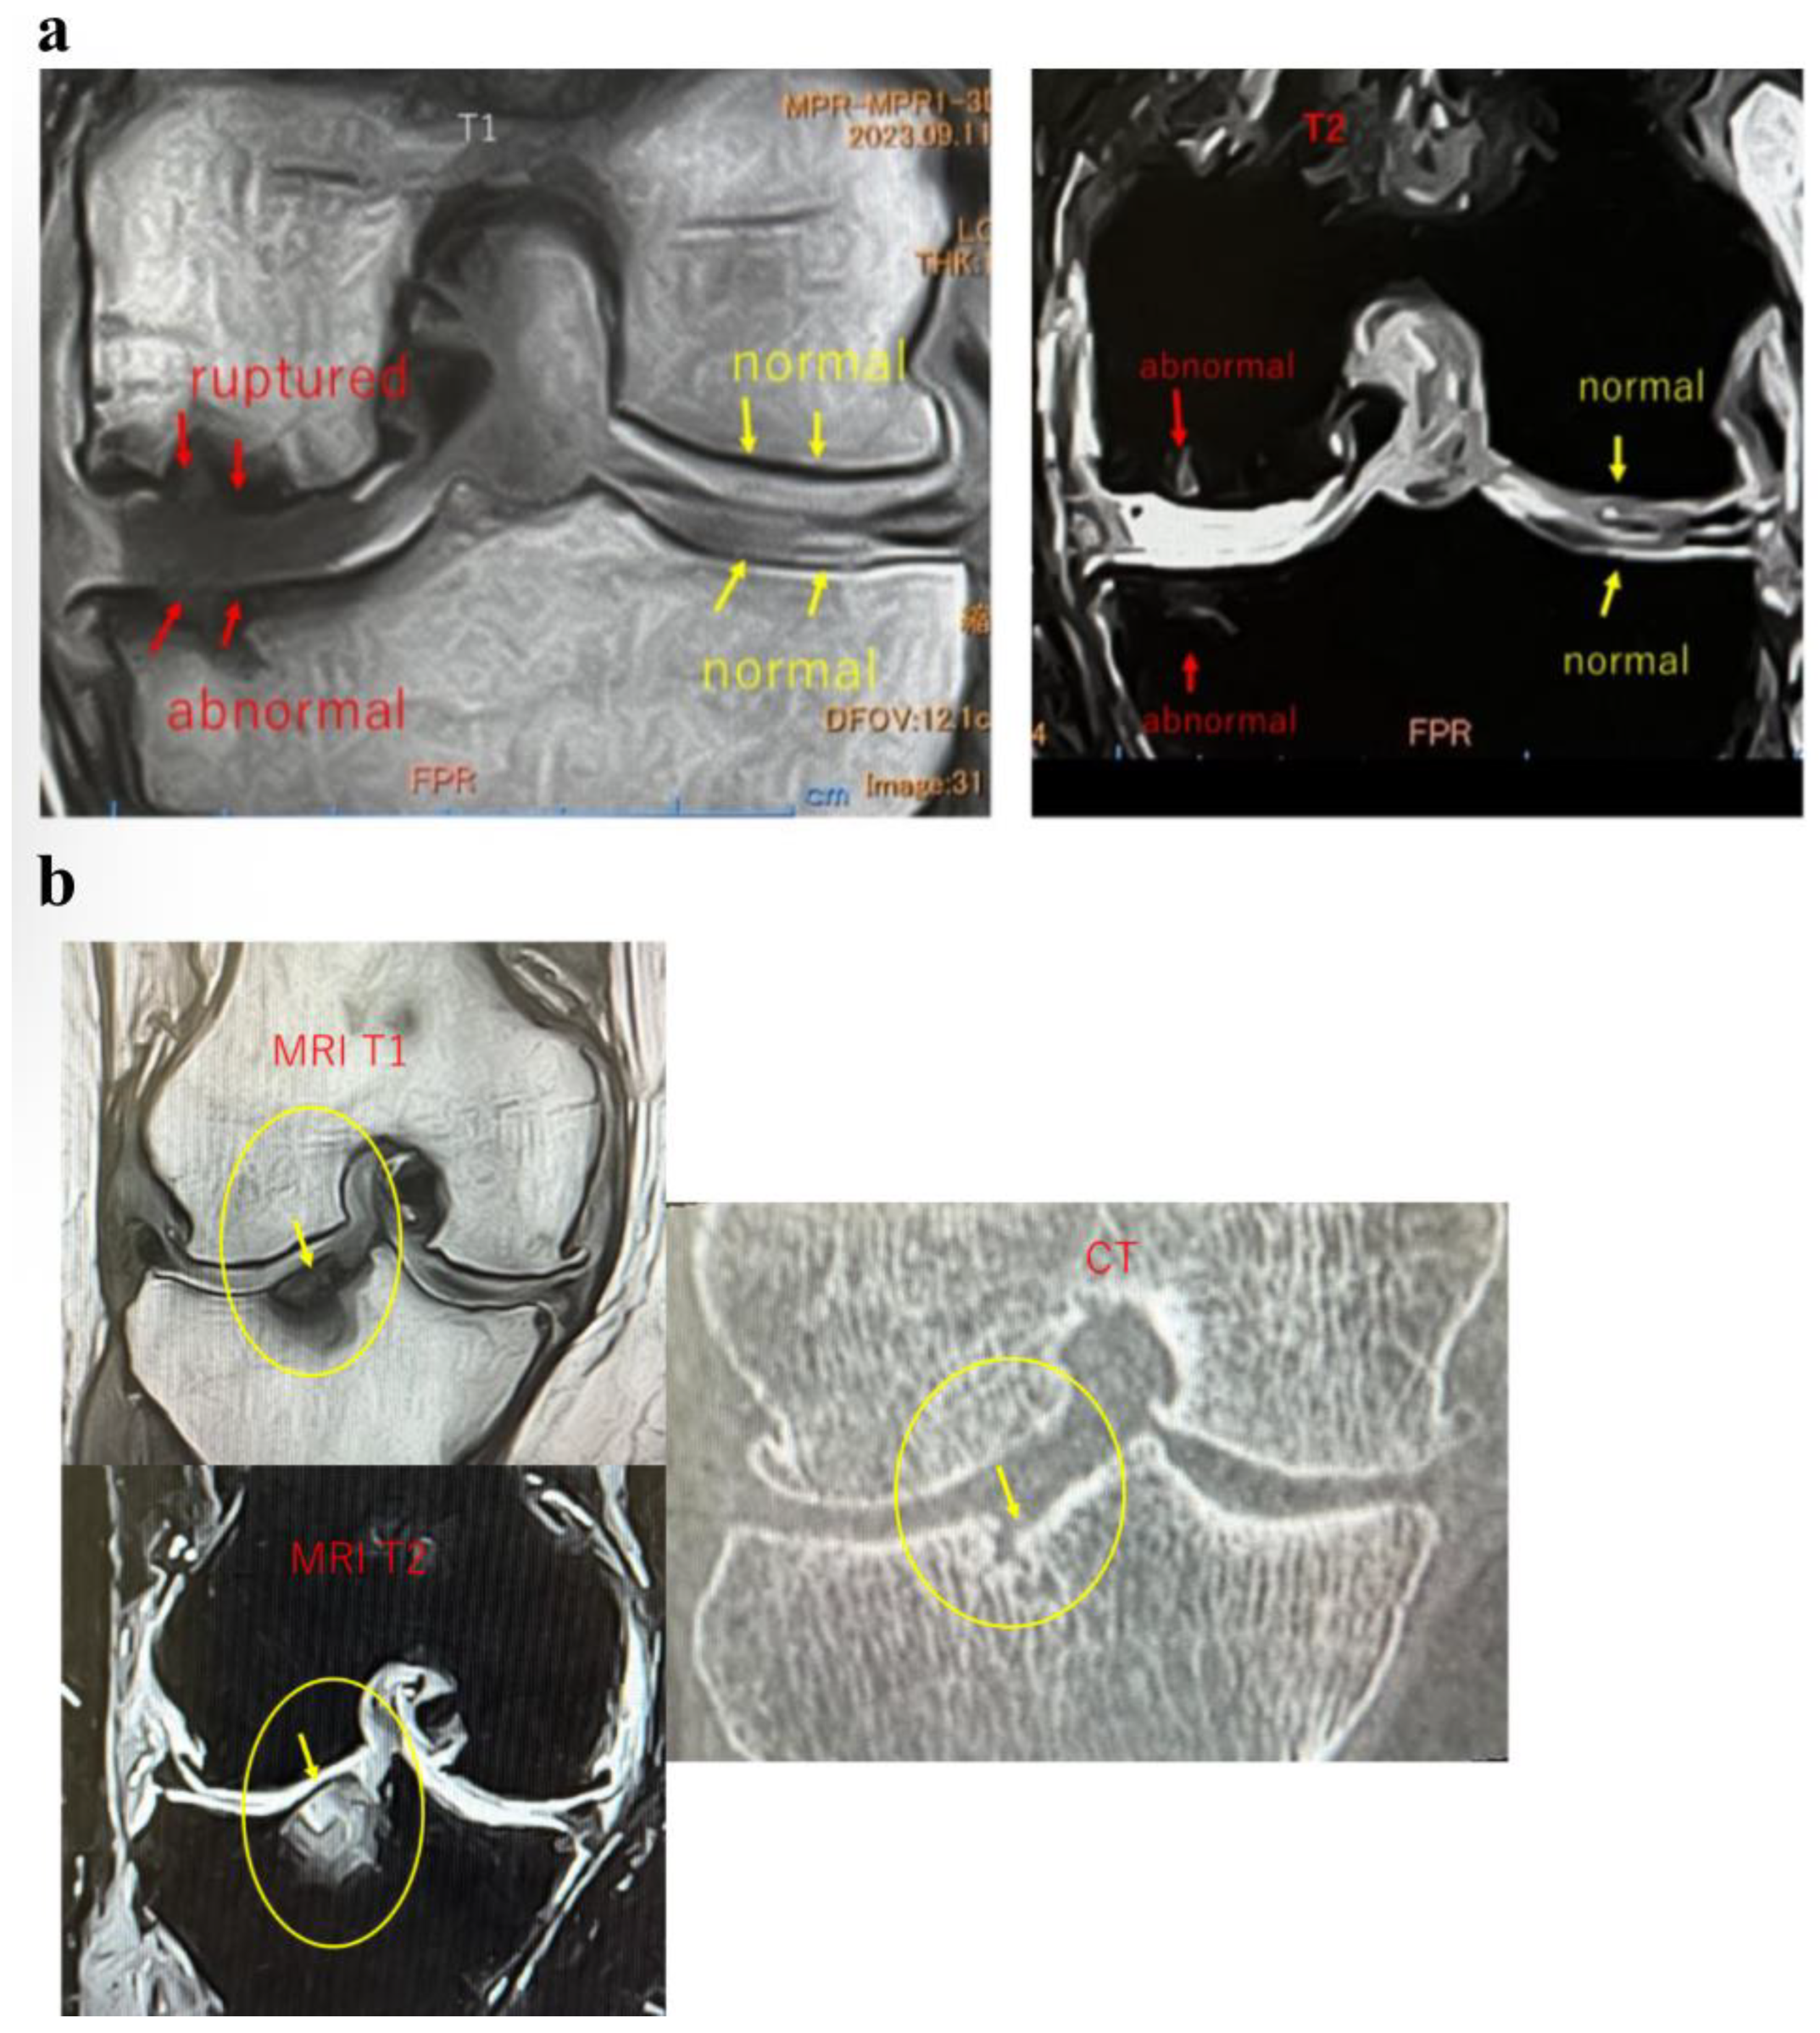

Case Reports

In Case 3 (Figure 8), a 70-year-old male, at baseline, MRI revealed the disappearance of the cartilage layer and SBP tear associated with a BML in the medial femoral condyle and tibial plateau. At 1-month post-treatment, mosaic-like high-signal areas extended throughout the region surrounding the BML. At 4 months, the mosaic-like areas and a reduction in BML were observed. At 7 months, although no improvement in the cartilage layer was detected, areas of bone sclerosis had expanded to cover the joint surface, indicating progression of bone repair. It was considered that the repair process was still in progress.

Figure 8.

Temporal MRI changes after treatment. At baseline, a BML with cartilage layer loss and SBP tear was observed in the medial femoral condyle and tibial plateau. At 1 month, mosaic-like high-signal areas spread around the BML. At 4 months, BML reduction and mosaic-like changes were seen. At 7 months, no cartilage recovery was evident, but bone sclerosis expanded to cover the joint surface.